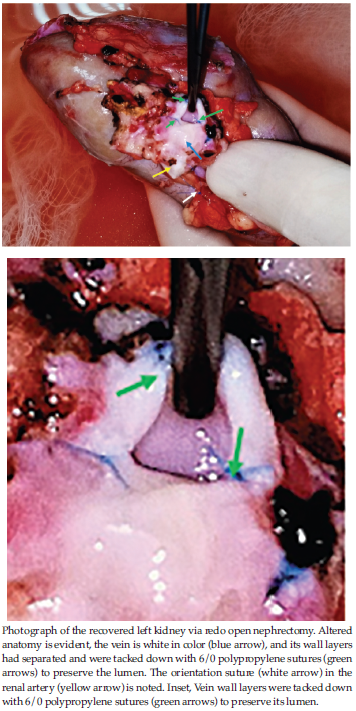

In the donor open nephrectomy, as expected, the perirenal tissue planes were obscured by dense adhesions, and the hilar structures were approached with great care. After 7 hours of painstaking dissection, we were able to salvage a graft with an unusual appearance (Figure 2).

The renal vein, which is normally blue in color, was white, with separation of the layers of its wall; which had to be tacked down with 6/0 polypropylene sutures to preserve the lumen to enable anastomosis ((Figure 2), inset). The artery and vein were both essentially the same color, and minimal bench dissection was carried out to avoid any inadvertent vascular damage.

The difficulty in dissecting this redo kidney and its hilum is reflected in the long duration of time that it took (7 hours) to complete. Donor nephrectomy is technically more demanding than routine nephrec-tomy because, in this case, the artery and vein need to be preserved for implantation. When tissue planes are obscured, as in our donor, identifying and dissecting hilar vessels become extremely challenging, with the looming risk of vascular damage.3,4 The normally blue-colored vein in this case was white, indicating fibrosis of the vein wall, and redo dissection had resulted in separation of the layers of its wall, which needed to be tacked down with 6/0 polypropylene sutures to preserve the lumen. The artery and vein were both the same color and indistinguishable; therefore, bench dissection was kept to a minimum to avoid inadvertent vascular damage.

Figure 2.Salvaged Graft with an Unusual Appearance